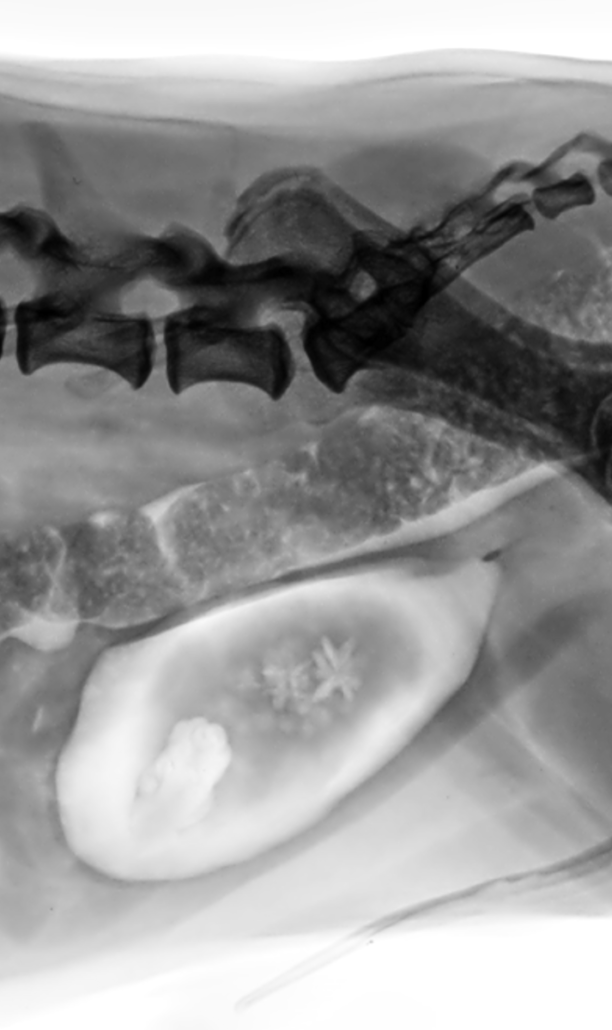

Cálculo y Pólipo urinarios

No todos los urolitos son radiopacos; por lo tanto, se recomienda que las imágenes de diagnóstico consistan en una radiografía abdominal. La ecografía puede identificar cálculos radiotransparentes como urato, xantina o cálculos pequeños de cistina. Sin embargo las radiografías son más precisas para ayudar a predecir el tamaño del cálculo si este es radiopaco. Los cálculos de estruvita son menos radiopacos que aquellos con calcio en su composición como los de oxalato de calcio